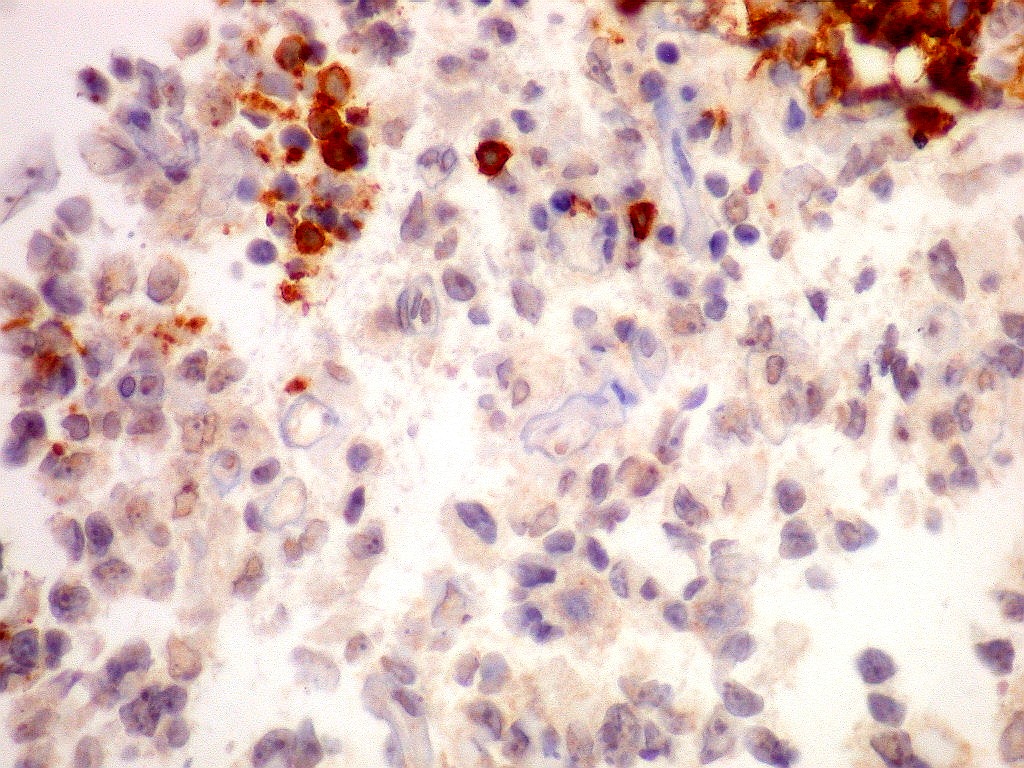

Tumor teratóide rabdóide atípico de III ventrículo.

7.  CD3, CD20, CD68, CD34

CD68.        Marca numerosos macrófagos no tumor, indicando alto turnover celular e  morte de muitas células neoplásicas, que são fagocitadas pelos macrófagos.

CD34.      Positivo só nos vasos, mostra  capilares bem distribuídos.  Células neoplásicas são negativas.